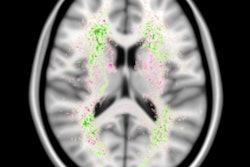

"In our study, we showed that sex differences are manifest regarding negative associations of total body fat percentage with regional subcortical gray matter volumes, including the globus pallidus and caudate nucleus, which have been associated with the reward circuitry of food-related stimuli," wrote the researchers led by Dr. Ilona Dekkers from Leiden University Medical Center in the Netherlands.

Other MR imaging studies have linked body mass index to lower gray-matter volume and white-matter integrity, while some research has suggested that structural differences in certain brain regions could play a role in regulating one's eating habits.

Taking it one step further, the Dutch researchers hypothesized that "lower volume of brain regions or decreased microstructural integrity of tracts involved in the neuronal regulation of the food-reward circuitry might also be associated with obesity."

In comparing the two genders, the researchers found that among men, 5.5% more total body fat was associated with 27 mm3 smaller globus pallidus volume. With women, 6.6% greater total body fat was associated with 11.2 mm3 smaller globus pallidus volume. The association between total body fat and globus pallidus volume was significantly lower in women than in men (p = 0.001).